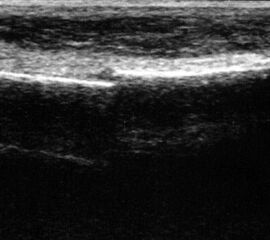

Längsschnitt über dem Lig. fibulocalcaneare. Die Peronealsehnen erscheinen als echoreiche runde bis ovaläre Struktur.

Abbildung 19

Lagerung: Rückenlage, OSG in Neutralstellung.

Schnittebene: LS über Lig. fibulocalcaneare.

Referenzstrukturen: Fibulaspitze und Talus.

Befunde: Das Lig. fibulocalcaneare is nativ schlecht abgrenzbar, da es in die Tiefe und nicht parallel zum Schallkopf verläuft. Direkt über das Band ziehen quer getroffen die Peronäussehnen. Durch die Distorsion kann auch das Peritendineum peroneale einreißen. Die Peronealsehnen sind dann in ihrer Sehnenscheide von Blut umgeben, was sich als echoarmer Ring (Halo-Phänomen) darstellt und ein indirektes Zeichen für eine Verletzung des Lig. fibulocalcaneare ist.